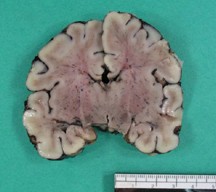

Ulegyria

- preferential damage of cortical sulci with preservation of gyri

- rare in adults but characteristic of term HII, especially in watershed areas

Watershed Infarcts

- infarction of parasagittal cortex between anterior, middle, and posterior cerebral arteries

- common in asphyxiated term infants

- manifests as ulegyria

- from prolonged hypoxic-ischemic insult